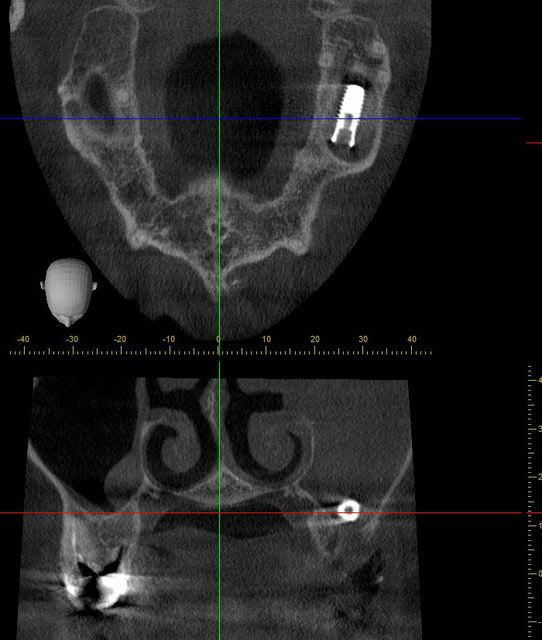

je crois que c'est plus raisonnable car le sinus est totalement bouché.

je ne l'avais pas encore vu avant d'étudier la tomosynthèse.

13/01/2013 à 12h34

à propos de l'implant en lui même, je vous ai fait une petite animation à partir du wiever de ma Morita.

( c'est trop bon d'avoir un cone beam au cabinet

mouarfff :)) )